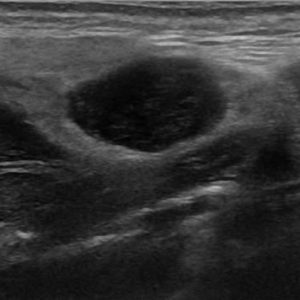

U tuyến nước bọt

Lượt xem: 138» 19-01-2021 -